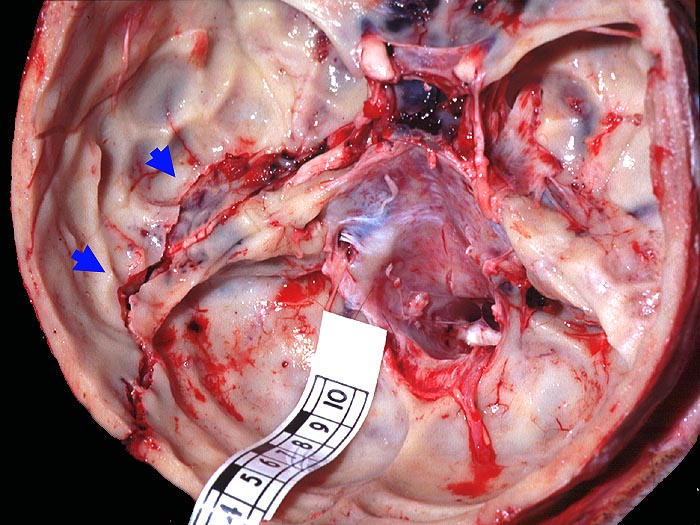

Makroskopie

Befund

Pathologischer Befund

Normalbefund